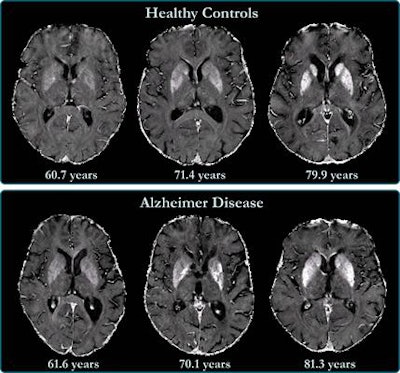

MRI scans show that accumulated iron in the outer layer of the brain is linked to cognitive deterioration in people with Alzheimer's disease, according to a study published on 30 June in Radiology.

Previous studies have linked high levels of brain iron with Alzheimer's disease, wrote a team led by Dr. Anna Damulina, also of the university: Iron deposits are associated with beta amyloid, a protein that forms plaques between neurons and disrupts brain function, as well as tangles of another protein called tau that also collects inside neurons. But these studies have focused on the deep gray-matter structures of Alzheimer's patients rather than the outer layer of the brain called the neocortex.

The study found higher iron deposits in the Alzheimer's patients' deep gray matter, total neocortex, and in the temporal and occipital lobes compared to healthy controls.